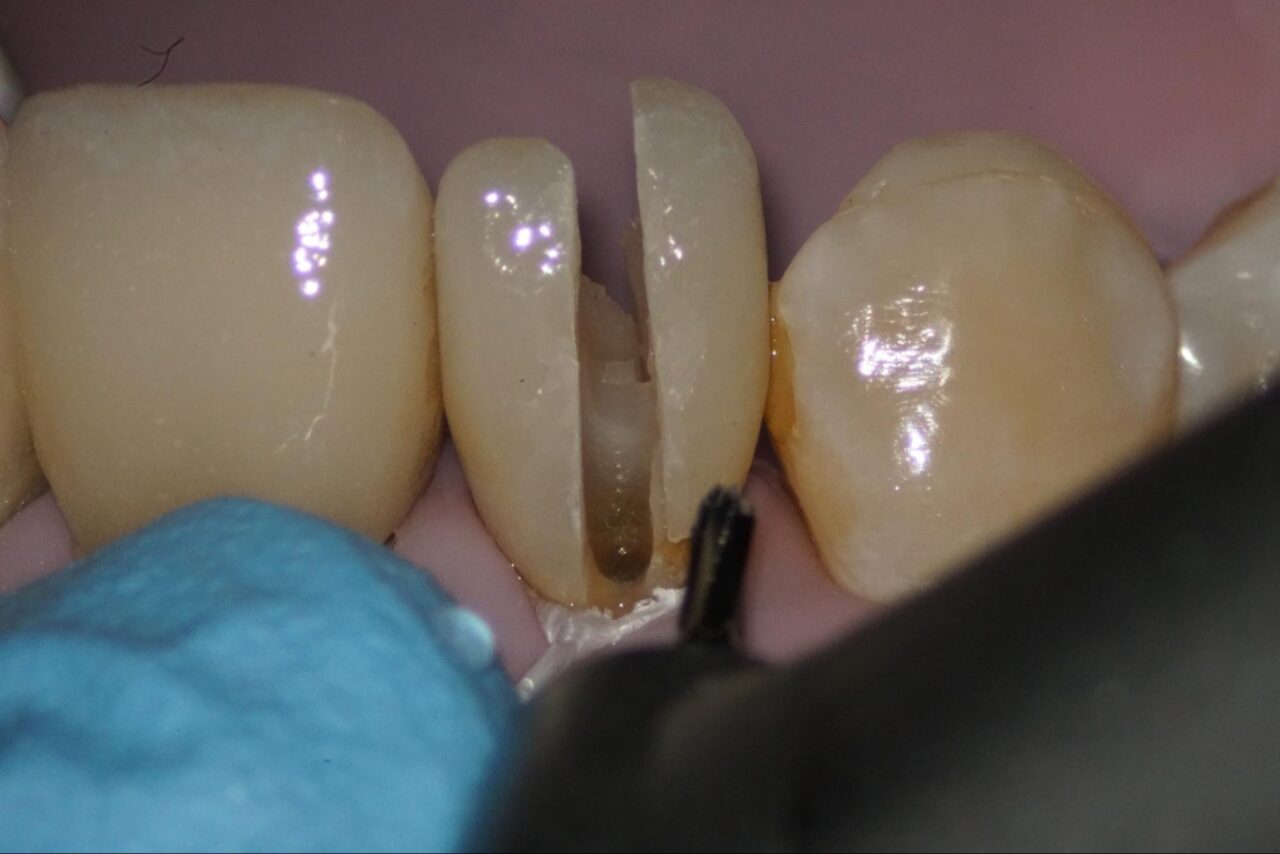

ファイバーコアを除去していきます。

余分な健全歯質をできるだけ削らないように拡大視野の中で丁寧に人工物や感染歯質を削っていきます。

感染部がグリーンに染まるカリエスディテクターを用いながら削っていくと頰側にクラックが入っている事が確認できます。